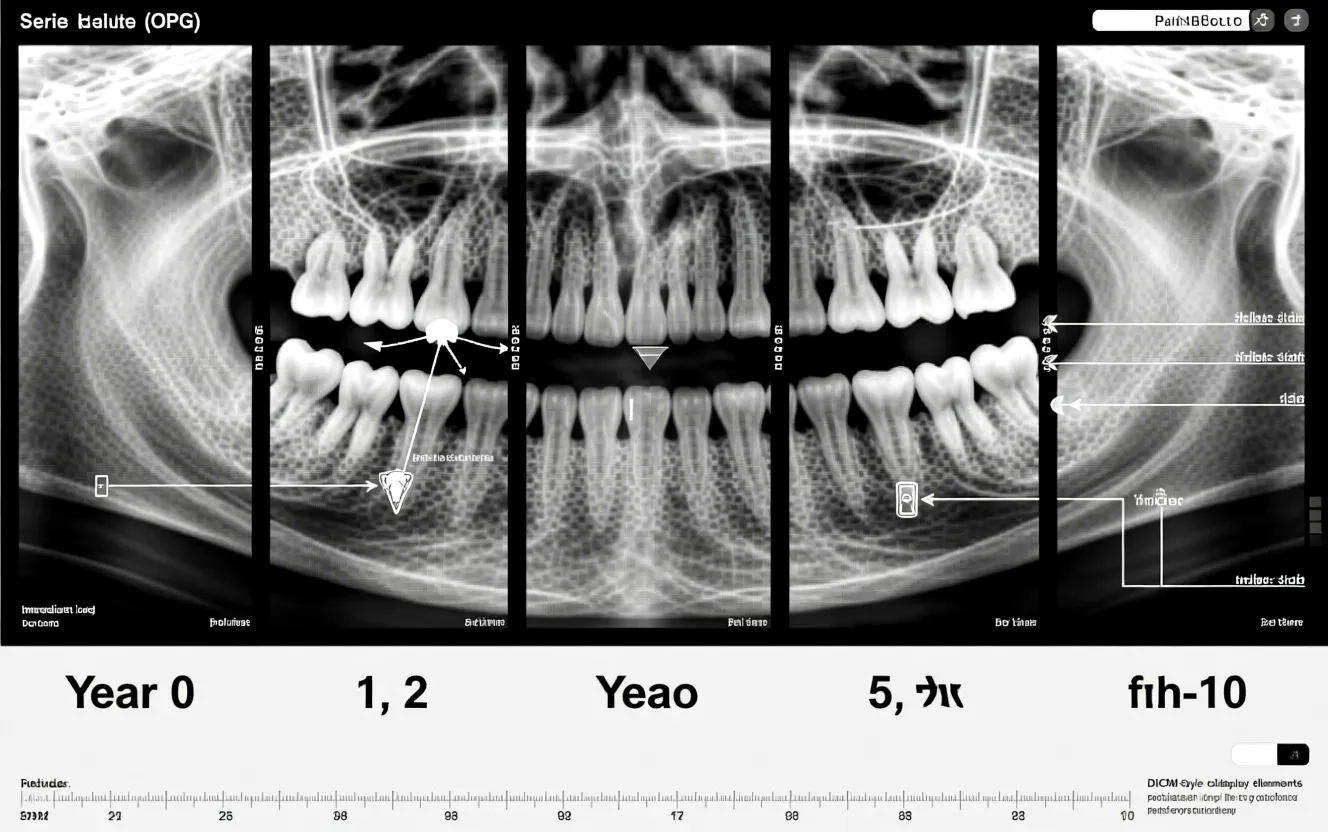

Les contrôles radiographiques péri‑opératoires et à long terme restent l'outil de référence pour mesurer la perte osseuse marginale. Dans des séries bien conduites, la perte osseuse marginale est souvent modeste et compatible avec la pérennité prothétique — mais des variations individuelles existent et la surveillance régulière (6–12 mois la première année puis annuelle) est recommandée.